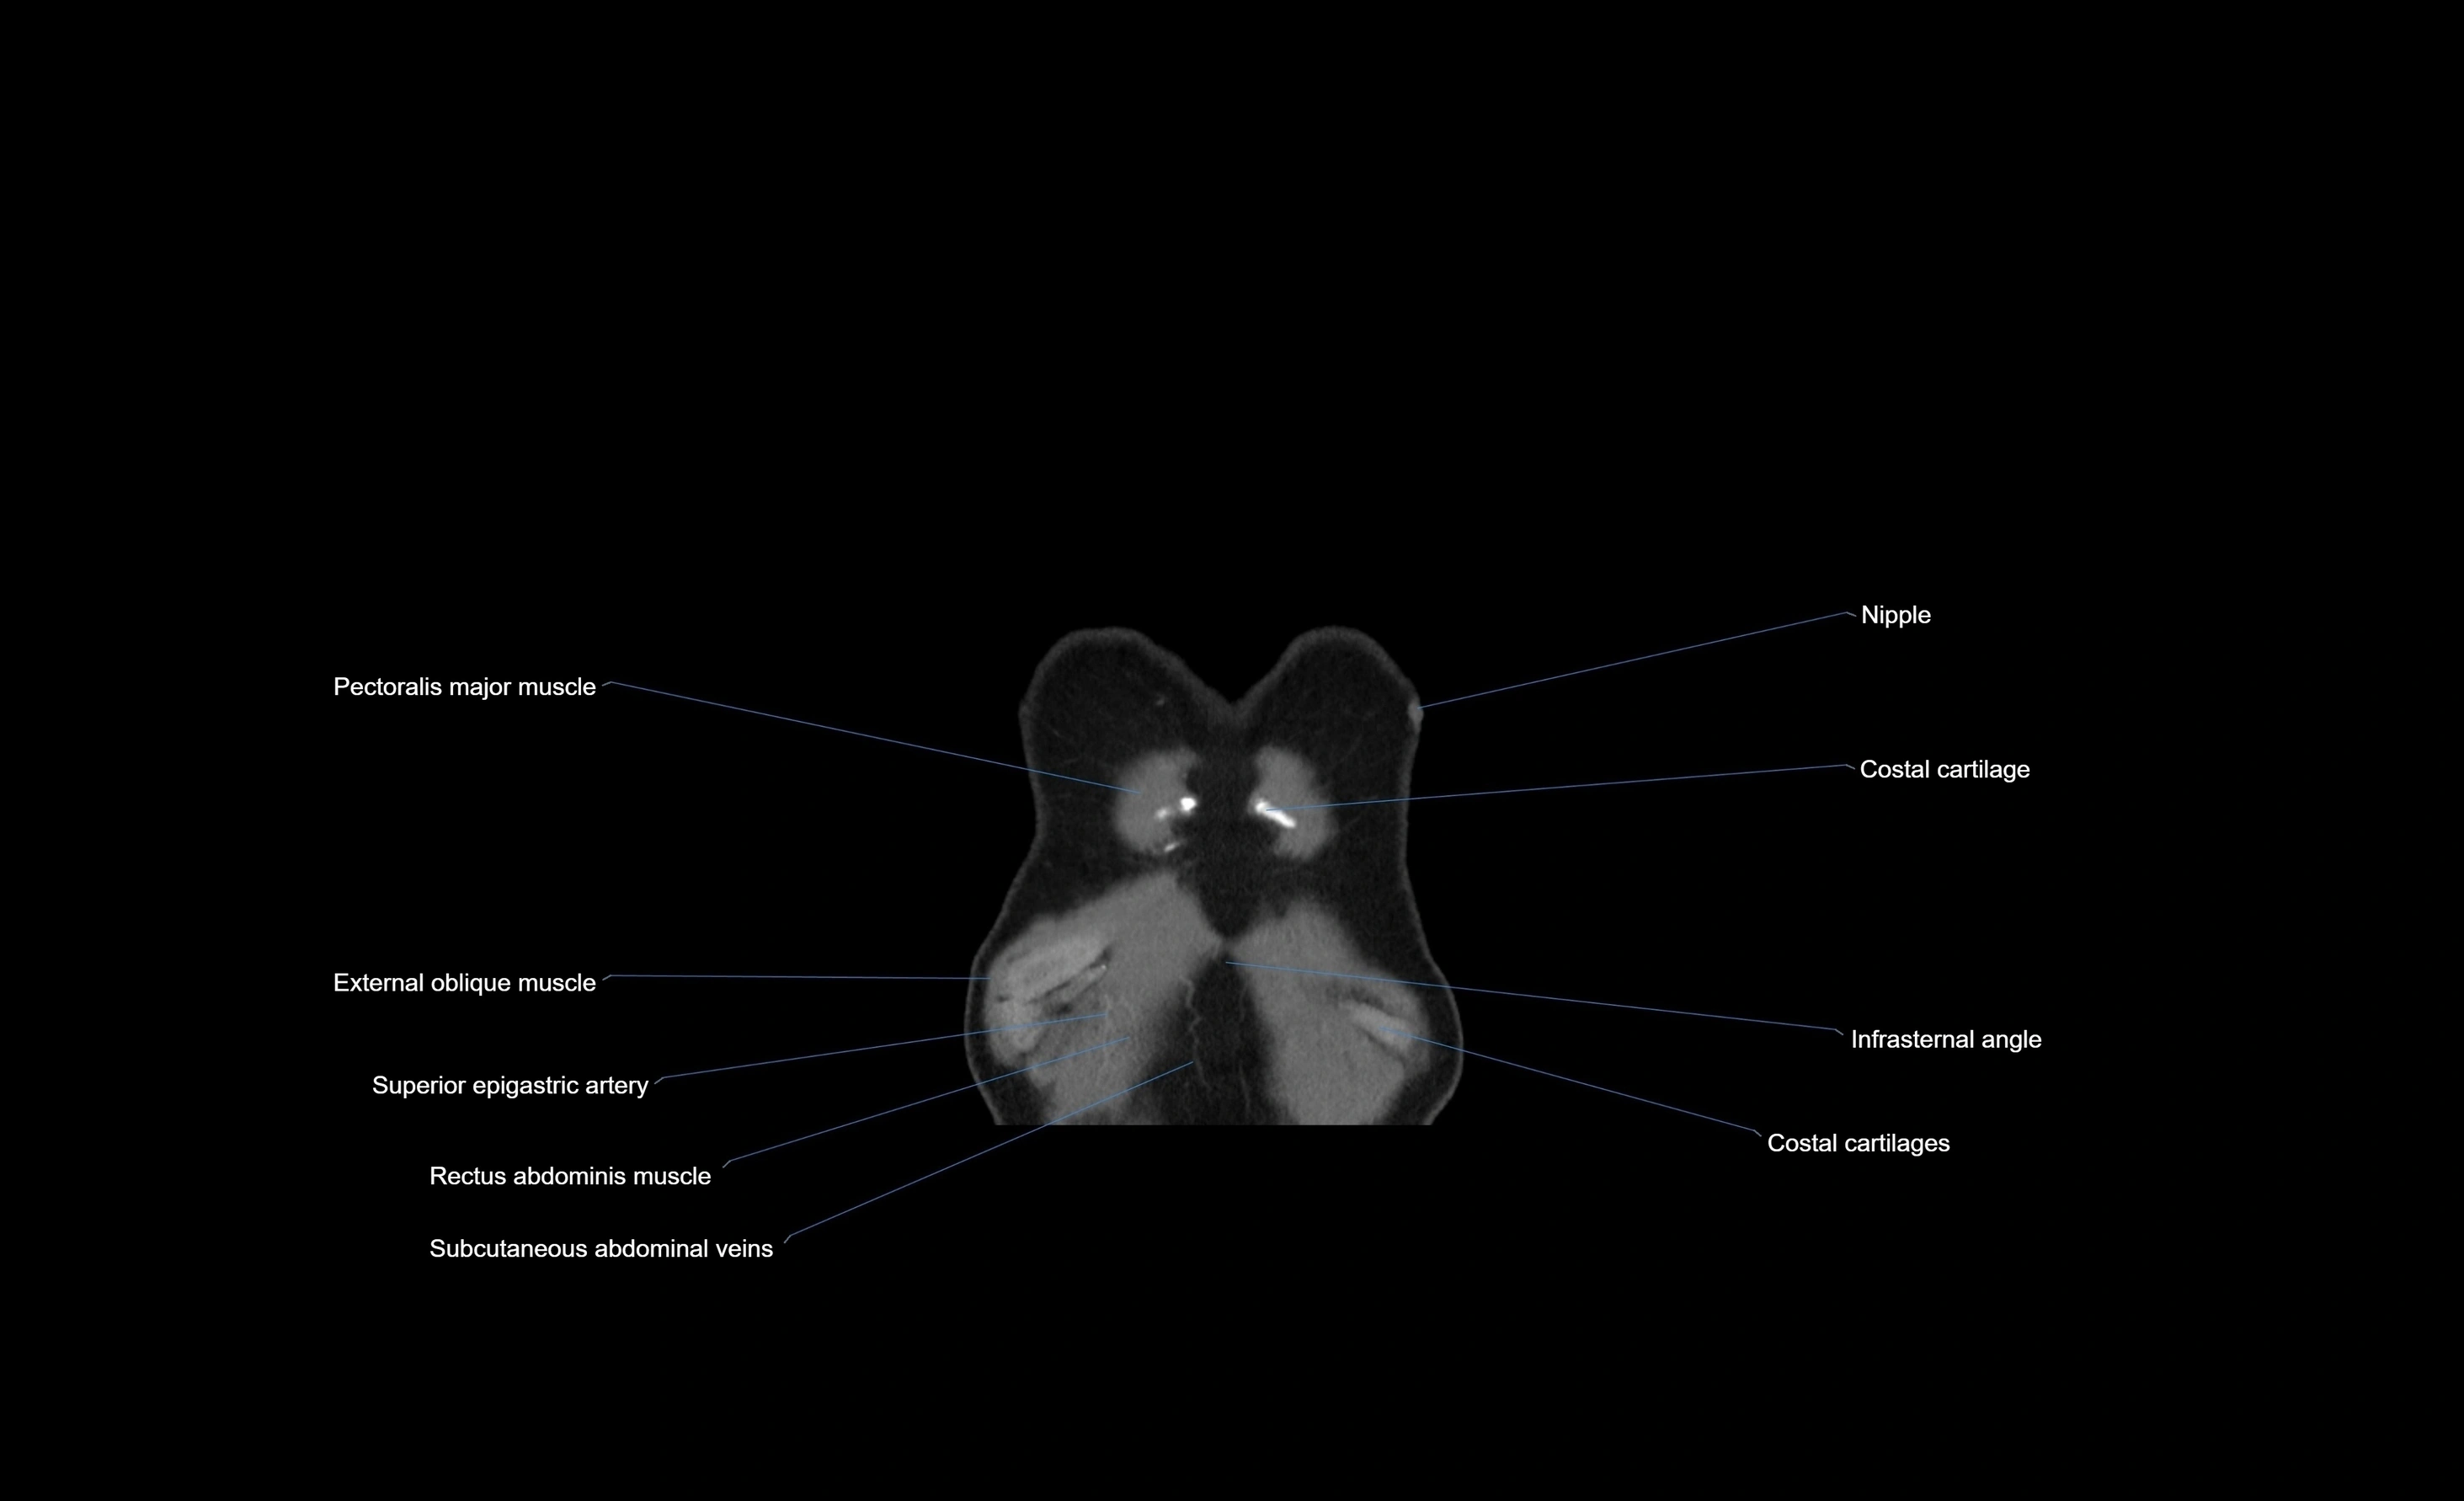

MRI images